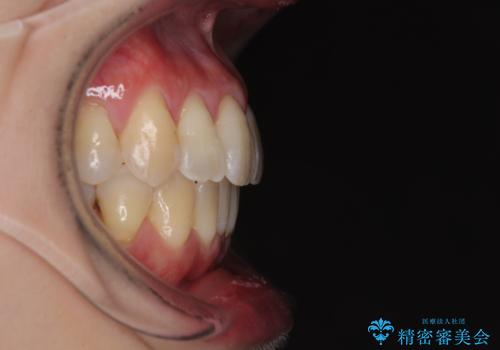

前歯のデコボコをインビザラインで目立たずに改善

- 上下前歯のデコボコを気にして来院された患者様です。

デコボコは顕著であるものの、口元の突出感は強くないため、非抜歯にて矯正治療を行うこととしました。

元々の叢生と歯肉退縮傾向になる歯肉であったため、ブラックトライアングルが目立つことが想定されました。

治療過程でブラックトライアングル改善のため、IPR(歯と歯の間を削る)を活用しました。